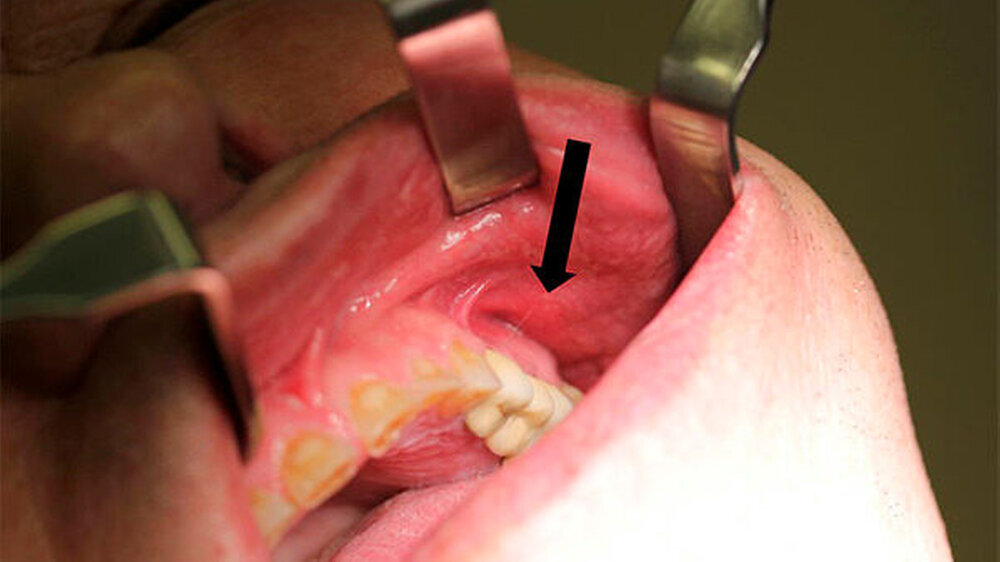

Da er sich bei dem Sturz bis auf eine kleine punktuell blutende Hautverletzung im Bereich der Oberlippe links keine größeren Verletzungen zugezogen hatte, schenkte er dem Vorfall vorerst keine weitere Beachtung. In den nächsten Tagen entwickelte sich daraus jedoch eine schmerzhafte Wangenschwellung links mit persistierendem Eiteraustritt aus der kleinen Wunde im Bereich der linken Oberlippe (Abbildung 1). Dies veranlasste ihn schließlich am fünften Tag nach dem Unfall einen HNO-Arzt aufzusuchen, der ihn zur Behandlung einer beginnenden Wangenphlegmone und zum Ausschluss einer Mittelgesichtsfraktur in unsere Klinik überwies.

Die klinische Untersuchung zeigte intraoral eine derbe, druckdolente, nicht verschiebliche, abgekapselte Schleimhautschwellung vestibulär regio 23 bis 27 (Abbildung 2) mit putridem Ausfluss aus einem Fistelgang nach extraoral im Bereich der Oberlippe links.